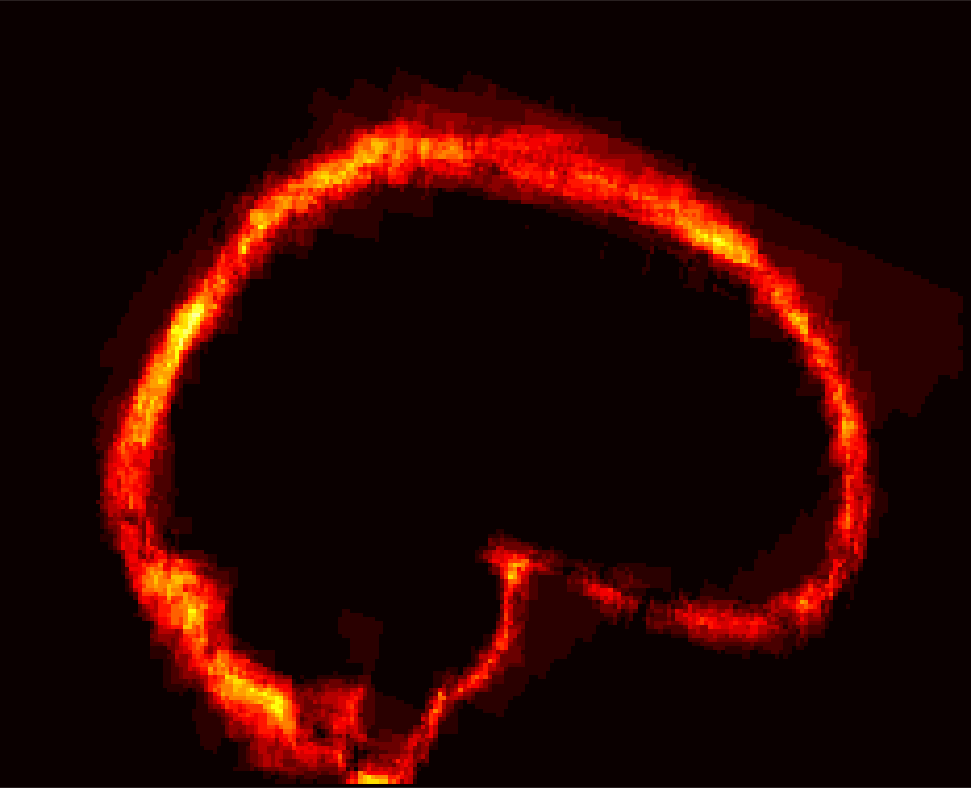

Fig. 1 shows example images from each dataset to illustrate image variability. IBSR and LPBA40 contain images from normal subjects and include large portions of the neck; BRATS has very low out-of-plane resolution; and the TBI dataset contains large pathologies and abnormal skulls.

Refer to caption

Figure 1: Illustration of image appearance variability on a selection of images from each (evaluation) database. From top to bottom: IBSR, LPBA40, BRATS and TBI.